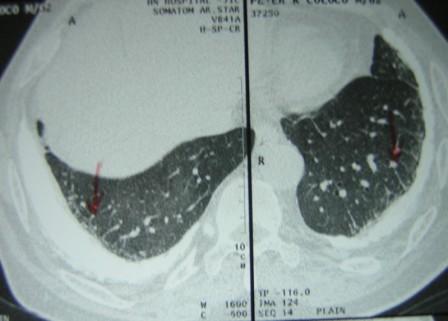

High Resolution CT scan of the lungs (Figure 2) showed bilateral pleural plaques, diffuse pleural thickening and increased interstitial markings. These changes were confirmed on prone films as well. (Figure 3) The calcified pleural plaques are particularly well seen on the mediastinal window of the CT scan (Figure 4).

Figure 3:High Resolution CT scan of the lungs in prone position.